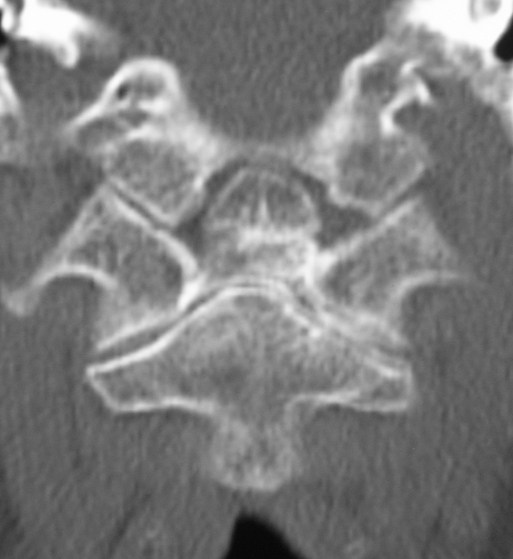

Koronal BT Kesiti - Os Odontoideum Aksiyal BT Kesiti - Atlas Füzyonu

Resim 3: Koronal BT kesidinde (sol) densin sklerotik kenarlarla ayrı bir kemik haline gelerek (=os odontoideum) C2 gövdesinden ayrışmış olduğu görülmektedir. Aksiyal BT kesidinde (sağ) os odontoideum'un atlas ön arkusuna kaynamış olduğu görülmektedir.